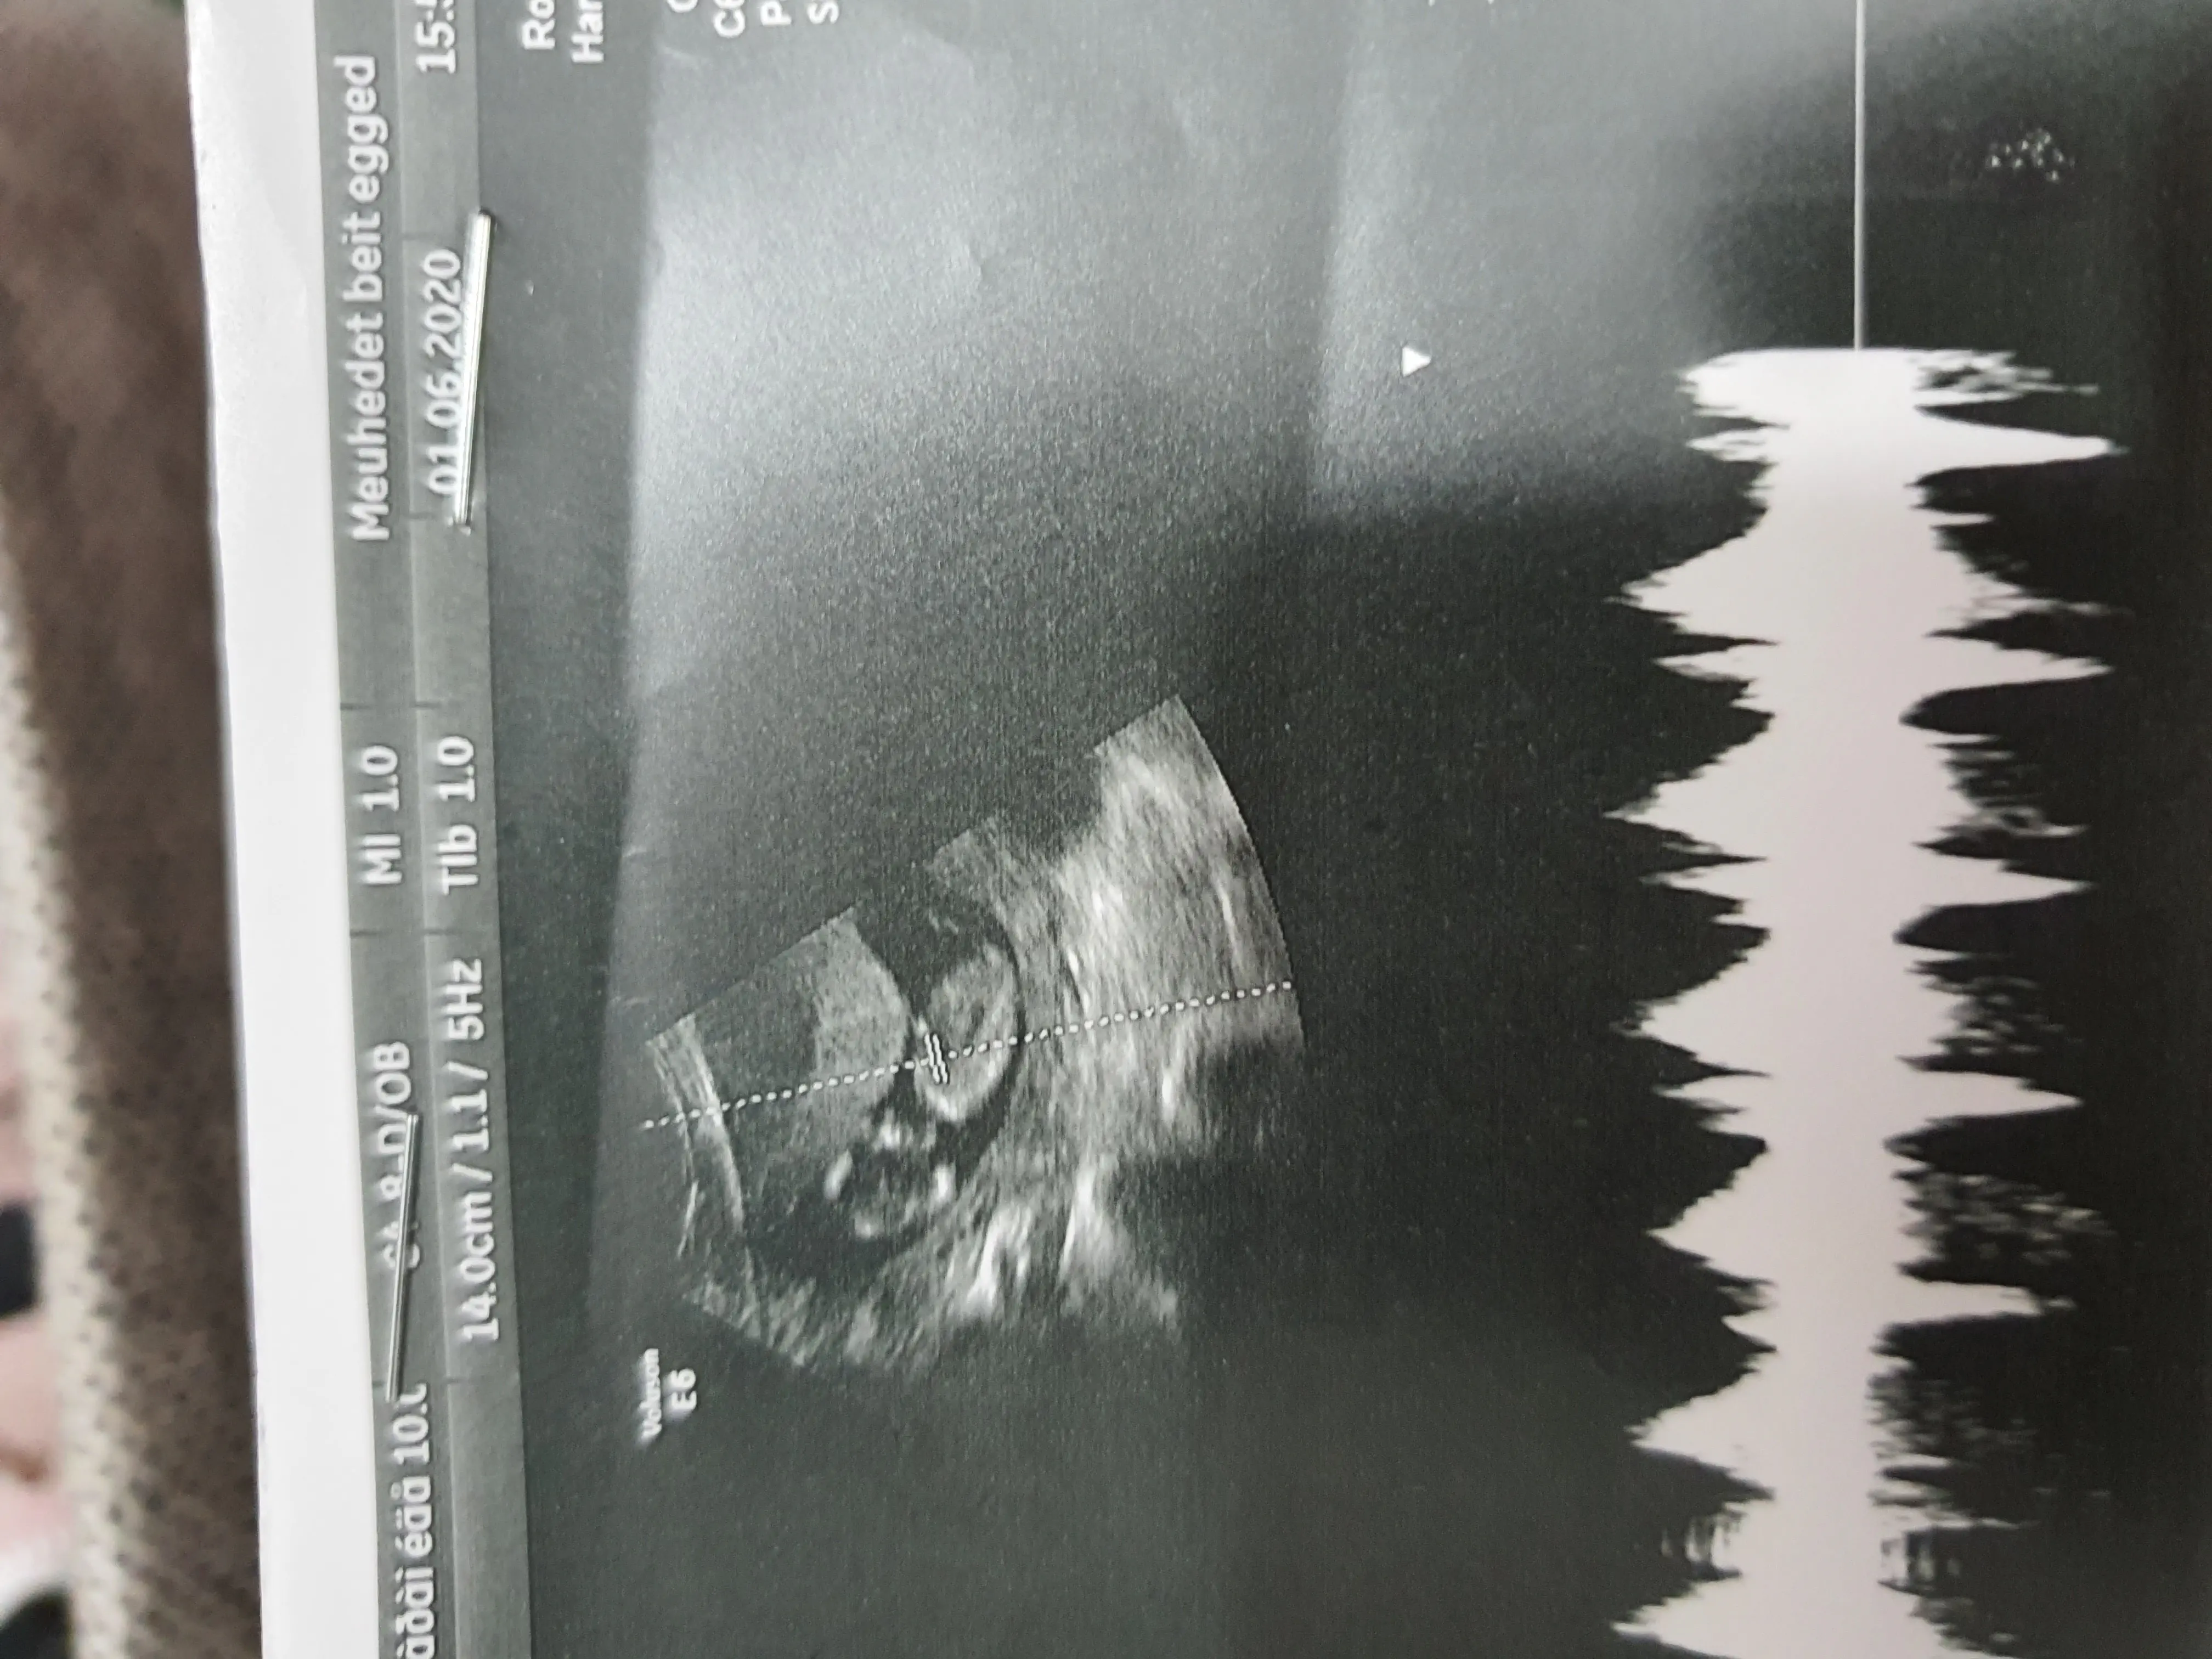

זה נספג לדםמיואשת******היו לי מאתמול צירים שראו במוניטור,

כאבי גב,התקשויות,לחצים באגן וכאב בבטן תחתונה.

(לפעמים זה בא ביחד ולפעמים הרגשתי רק אחד מהתסמינים)

היום בבוקר היו לי שוב כאבי גב,

זה עבר אחרי מנוחה.

בנוסף אני מרגישה חולשה,כנראה בגלל החום בחוץ.

זה מצב נורמלי בשבוע כזה?

אני כל פעם לא יודעת אם זה יוביל ללידה..

וחשוב לציין-שאני ממש משתדלת לשתות 2 ליטר מים כל יום..

יש לי היום שוב תור לרופא נשים,אבל מעניין אותי לשמוע מנסיונכן..

ההגדרה של צירים מוקדמים זה צירים לפני המועד. זה לא סותר את העובדה שלא מנסים לעצור לידה.

והשאלה היא איך אפשר לדעת שזה צירים אמיתיים ושכבר צריך ללכת ללדת?

אם אני מרגישה את הצירים שונים,פעם כאבים בגב,פעם התקשויות של הבטן,פעם לחצים באגן..

זה נורא מבלבל.

בלידה הקודמת היו לי צירים כואבים בגב והתקשויות של הבטן אז היה קל לזהות שזה מוביל ללידה..